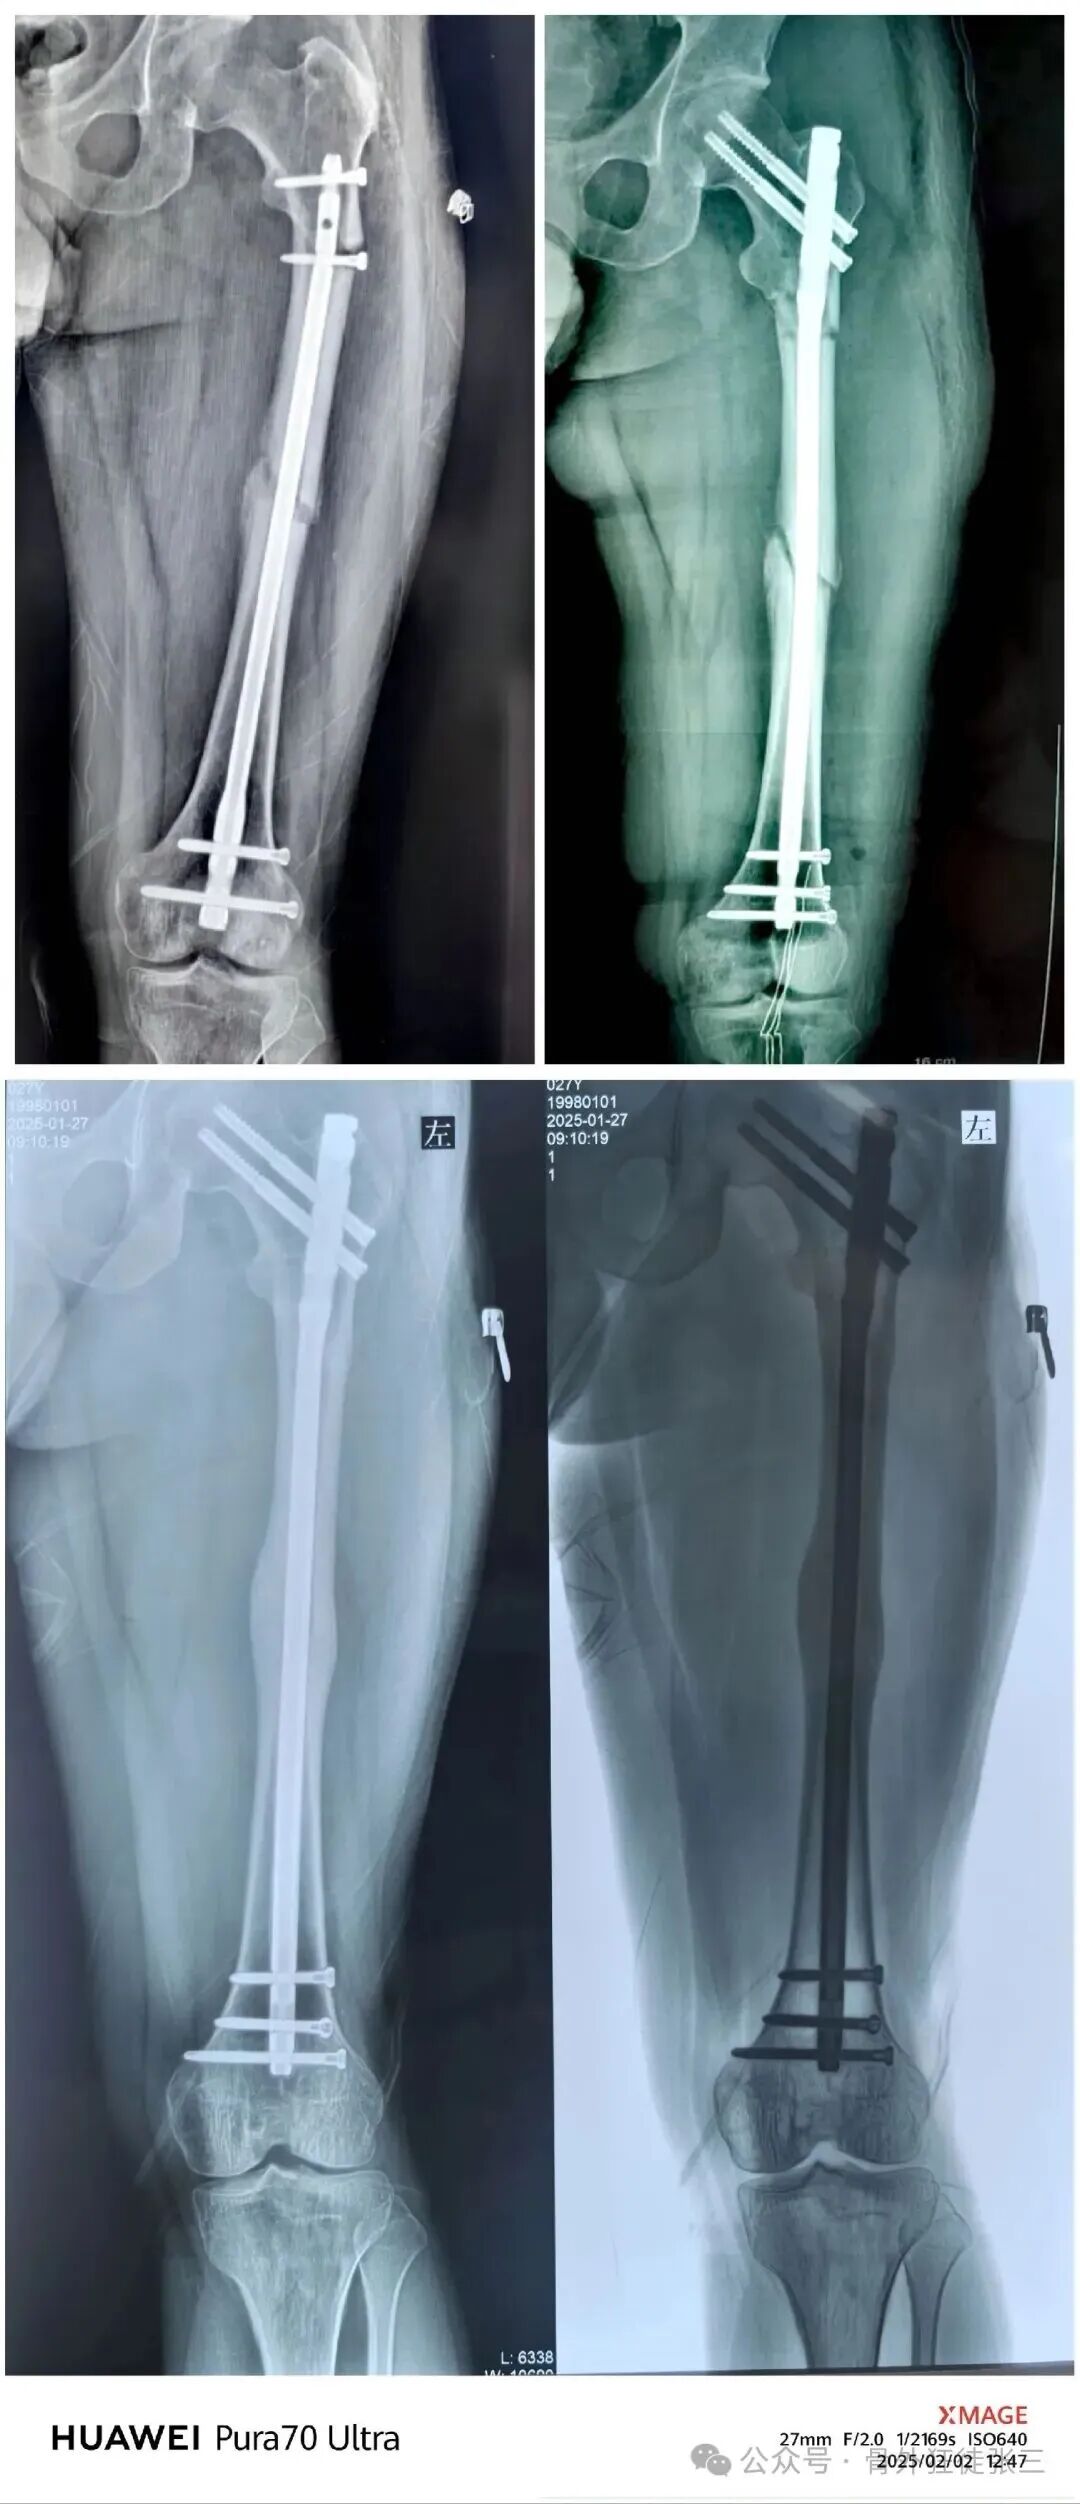

术后5个月完全愈合

这个患者术后14个月取了髓内钉

术后已经随访了两年